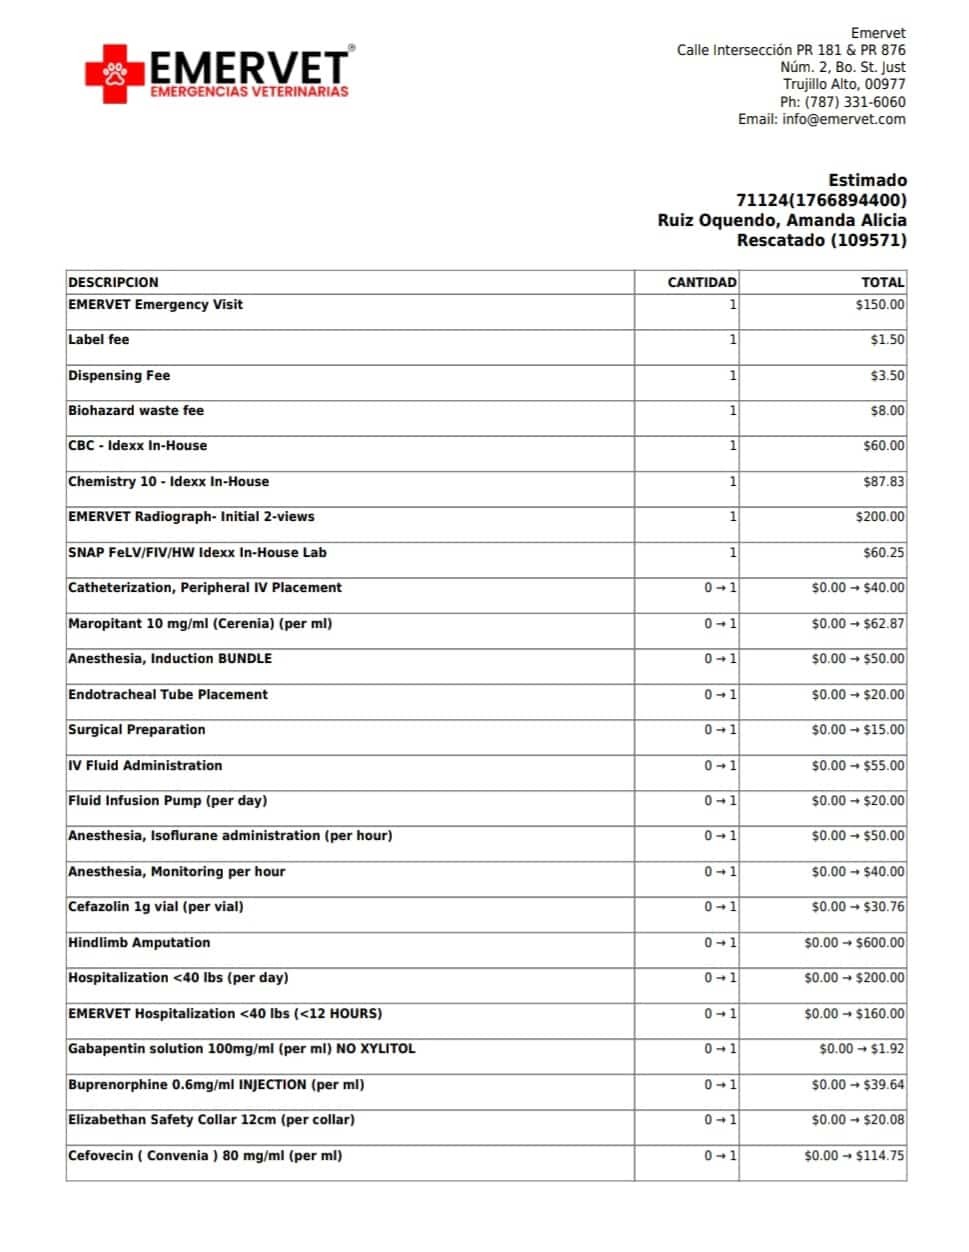

- Update se llevó al gatito a emervet 24/7 y el veterinario en turno nos explicó que para salvar al gatito hay que hacerle una amputación de su patita derecha el dinero que se está recaudando es para el pago de su operación y hospitalizacion también para medicinas y futuros tratamientos.

- The kitten was taken to Emervet 24/7 and the veterinarian on duty explained that to save the kitten, its right leg needs to be amputated. The money being raised is for the cost of its surgery and hospitalization, as well as for medicines and future treatments.